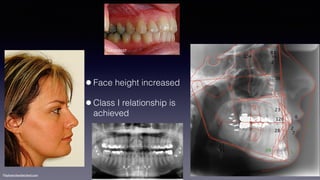

•Face height increased

•Class I relationship is

achieved